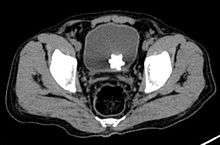

The diagnosis of bladder stone includes urinalysis, ultrasonography, x rays or cystoscopy (inserting a small thin camera into the urethra and viewing the bladder). The intravenous pyelogram can also be used to assess the presence of kidney stones. This test involves injecting a radiocontrast agent which is passed into the urinary system. X-ray images are then obtained every few minutes to determine if there is any obstruction to the contrast as it is excreted into the bladder. Today, intravenous pyelogram has been replaced at many health centers by CT scans. CT scans are more sensitive and can identify very small stones not seen by other tests.[8]

Jackstone calculi are rare bladder stones that have an appearance resembling toy jacks. They are almost always composed of calcium oxalate dihydrate and consist of a dense central core and radiating spicules. They are typically light brown with dark patches and are usually formed in the urinary bladder and rarely in the upper urinary tract. Their appearance on plain radiographs and computed tomography in human patients is usually easily recognizable. Jackstones often must be removed via cystolithotomy.[10]